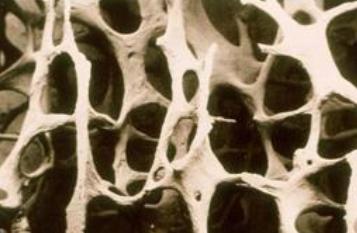

骨质疏松症是一种非常常见的骨骼疾病。 它是一种以草莓视频黄色成人降低、骨微结构破坏、骨痛、骨脆性增加、易骨折为特征的全身退行性疾病。 超声草莓视频黄色成人分析仪厂家骨质疏松症在50岁以上的中老年人群中很常见,尤其是绝经后的女性。 这是因为女性绝经后雌激素分泌减少,导致骨代谢紊乱,骨吸收远远大于骨形成,进而导致骨迅速流失,骨质疏松。

临床上,骨质疏松症的诊断通常基于草莓视频黄色成人(BMD)。 草莓视频黄色成人测试(BMD)可用于包括年轻人在内的所有骨质疏松风险人群,不仅可以诊断骨质疏松,还可以预测骨折的风险,尤其是髋部骨折。骨质疏松症的诊断需要通过草莓视频黄色成人(Bone mineral density, BMD)测量,这是基于BMD检查的t值。 根据草莓视频黄色成人测量结果对骨质疏松程度进行分级。 草莓视频黄色成人测量t值大于-1为正常; 当周期值在-1 ~ -2.5之间时,骨量减少; 当t值小于-2.5时,为骨质疏松; 当t值< -2.5合并脆性骨折时,为严重骨质疏松 。